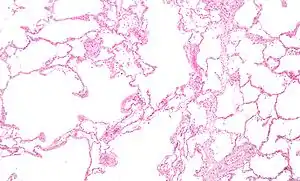

![]() Мікрографія емфіземи (ліворуч на зображенні великі пустоти) та легеневої тканини з відносним збереженням альвеол (праворуч). Фарбування гематоксиліном та еозином. Мікрографія емфіземи (ліворуч на зображенні великі пустоти) та легеневої тканини з відносним збереженням альвеол (праворуч). Фарбування гематоксиліном та еозином. | |